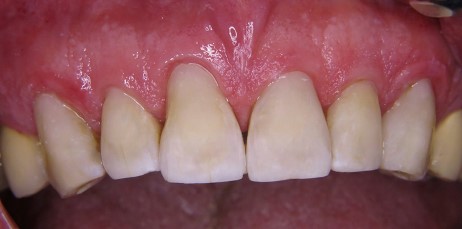

Z klinicznego punktu widzenia w zębach od 13 do 23 obecne były niezadowalające wypełnienia kompozytowe, z obecną szczeliną brzeżną i przebarwieniami. Ze względu na wiek pacjenta obserwowano także niewielkie przedsionkowe recesje bez podrażnienia dziąseł. Wszystkie zęby były żywe, wykazywały ruchomość I stopnia i brak wrażliwości na opukiwanie. Tylko ząb 11 został mniej więcej 2 lata wcześniej unieruchomiony i zszynowany adhezyjnie z zębem 21 poprzez wykonanie stałej szyny na powierzchniach podniebiennych (pasmo włókien szklanych GrandTEC, VOCO, GmbH, Cuxhaven). Po szczegółowym omówieniu z pacjentem planowanego adhezyjnego leczenia z użyciem materiału kompozytowego zaplanowano kolejną wizytę (ryc. 1).

Ryc. 1. Początkowa sytuacja kliniczna, niezadowalające wypełnienia w widoku od przodu.